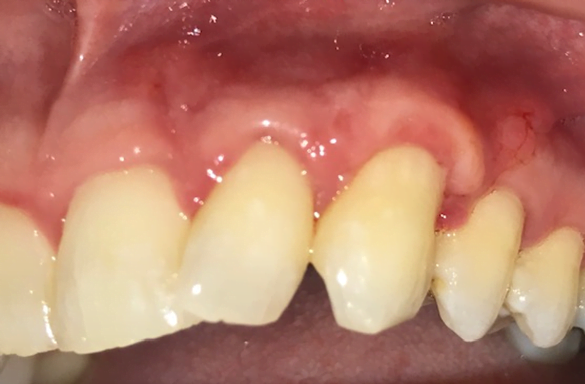

Gum grafting is a dental procedure conducted by Dr. Rivas and his team designed to restore the health and aesthetics of receding gums. Receding gums can cause various dental problems, including tooth sensitivity, tooth loss, and diminished self-confidence.

It involves taking tissue from one area of your mouth (the donor site) and placing it over the affected area (the recipient site). The purpose of this procedure is to strengthen and protect the exposed roots, enhance gum coverage, and improve the overall appearance of your smile.